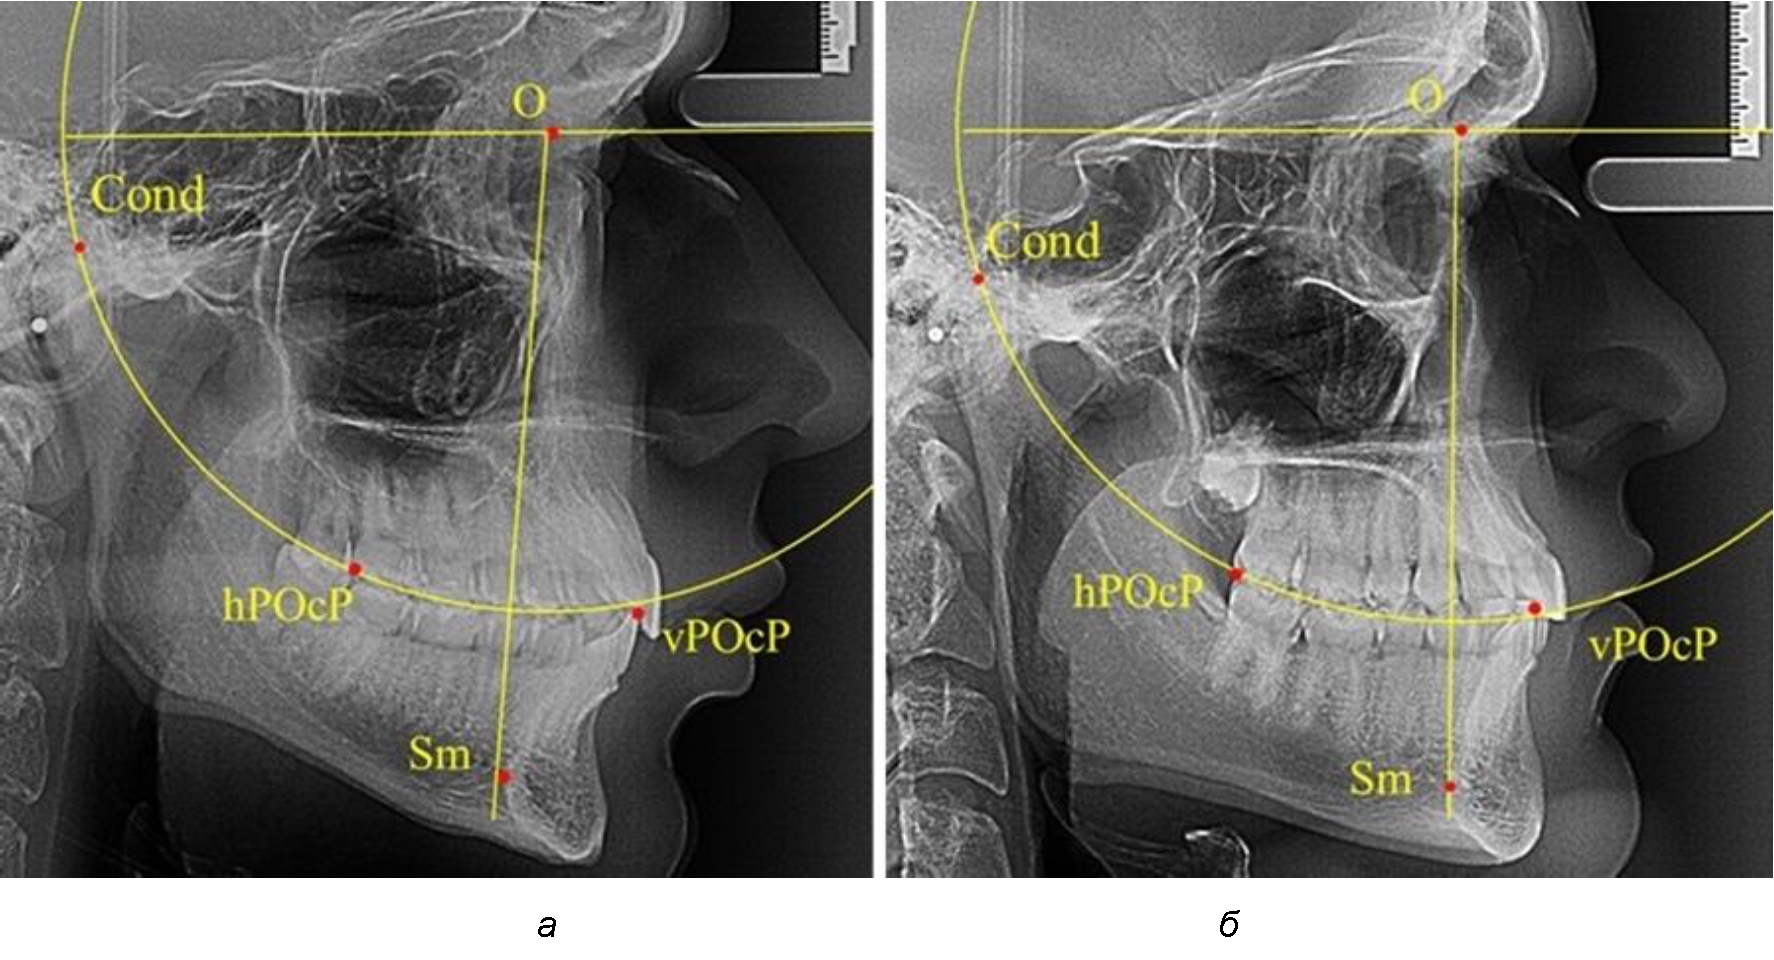

Результаты исследования рентгенограмм с мезотрузионным типом резцов показали, что линия Bimler проходила позади первых премоляров у людей с широким типом подбородочного выступа, однако окклюзия была физиологической и не требовала удаления премоляров, что носило рекомендательный характер при проведении подобных исследований при аномалиях прикуса. У людей со средними формами подбородочного выступа линия Bimler проходила впереди первых премоляров (рис. 2).

Аналогичная ситуация была у людей и с узкими вариантами подбородочного выступа.

Таким образом, при мезотрузионном типе зубочелюстных дуг расположение премоляра впереди линии Bimler при широких вариантах подбородка не может быть критерием выбора экстракционных методов лечения.

Рис. 2. Положение первых верхних премоляров при мезотрузии с широкими (а) и средними (б) размерами подбородка